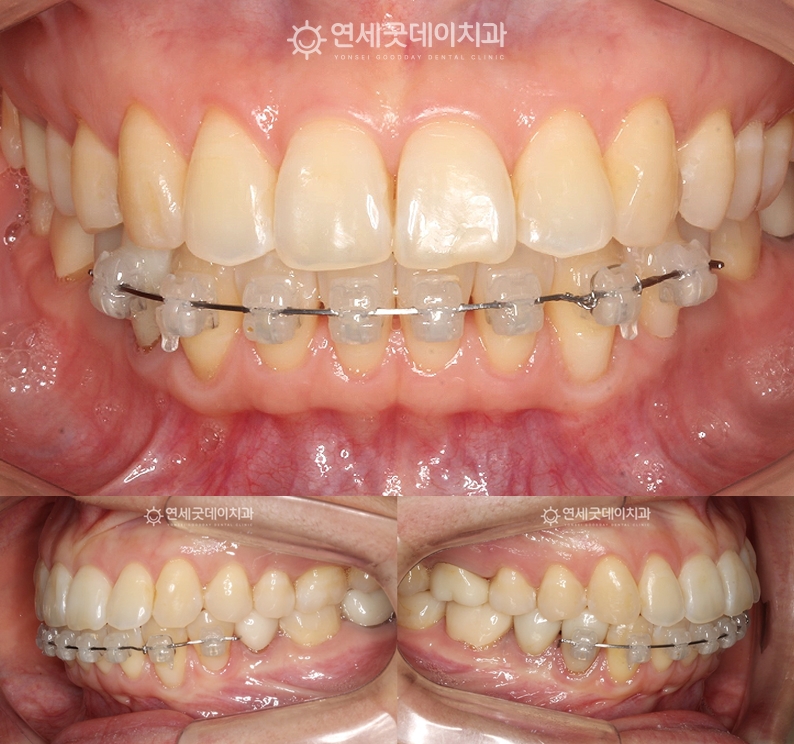

환자분은 #33 치아의 뿌리 방향을 조절하여 이 과정은 단순히 겉보기 배열이 아닌 11개월 간의 아랫니 부분 재교정을 진행하였으며

환자분의 경우, 치경부 마모를 개선하기 위해 이후 핀홀 잇몸이식과 엠도게인을 병행 적용하여

약 1달 후 경과 모습입니다. 치아가 올바른 각도에 재위치 하면서

교정 과정에서 나타날 수 있는 잇몸퇴축은 긴 치료 받으시느라 고생 많으셨습니다. ^^